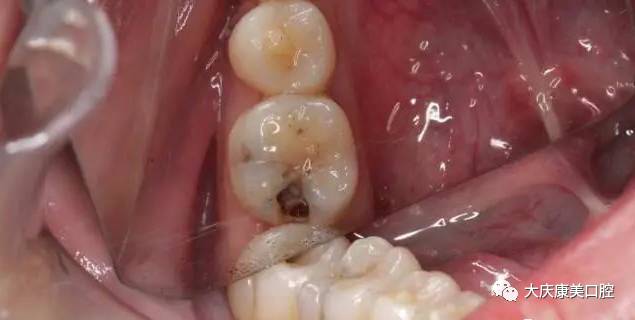

其实医生抽出的牙髓,就是牙神经!之所以抽神经,因为这是根管治疗最关键的一步,说明你的牙髓已经没得救了!牙齿即将烂掉!牙神经失去活力,没有感觉到牙痛。为了防止感染,只能抽掉牙神经,进行根管治疗。

肯!定!不!会!如果是蛀牙伤及牙神经的时候,不到迫不得已才会抽掉牙神经!随便抽掉牙髓,牙齿将会失去牙神经提供的营养,一旦牙髓没有活力,那跟死牙已经没什么区别了!时间一久牙齿还会老化变脆。

一旦患上牙髓炎或者根尖周炎,都得做根管治疗,抽掉牙神经!最后你对牙神经有什么疑问?